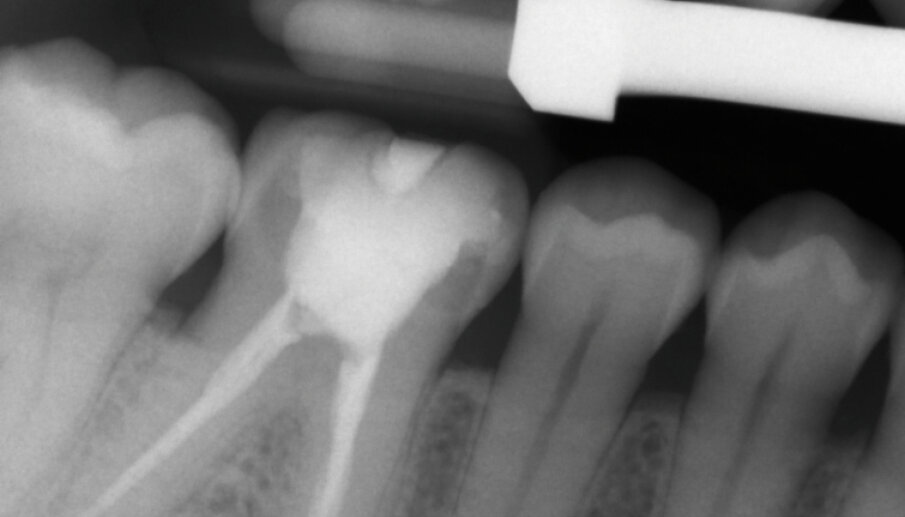

Fig. 13a: X-ray control image before and after the treatment

Fig. 13b: X-ray control image before and after the treatment

The adhesive (Tetric N-Bond Universal) was applied and dispersed with a strong stream of air. The dual-curing (DC) version of the Variolink Esthetic luting composite was used for seating due to the thickness of the crown and the low translucency of the ceramic material (Fig. 7). The luting composite was applied into the crown. Then the restoration was seated (Fig. 8) and light cured from each side for two seconds. Excess composite was easy to remove due to the Ivocerin photoinitiator, which provides a fast and thorough cure with a minimum amount of energy (Fig. 9). For final polymerization, the restoration was light-cured from each quarter for 20 seconds (Fig. 10). Figure 11 shows the oral situation after placement of the crown. Although the cement line is located above the gingival margin, it is not visible due to the favourable tone and opacity of the luting composite. Fig. 12 shows an X-ray control image of the restoration: the radiopaque build-up material and cement can be easily told from the tooth structure. This aspect is particularly important in situation where excess cement cannot be seen with the naked eye.